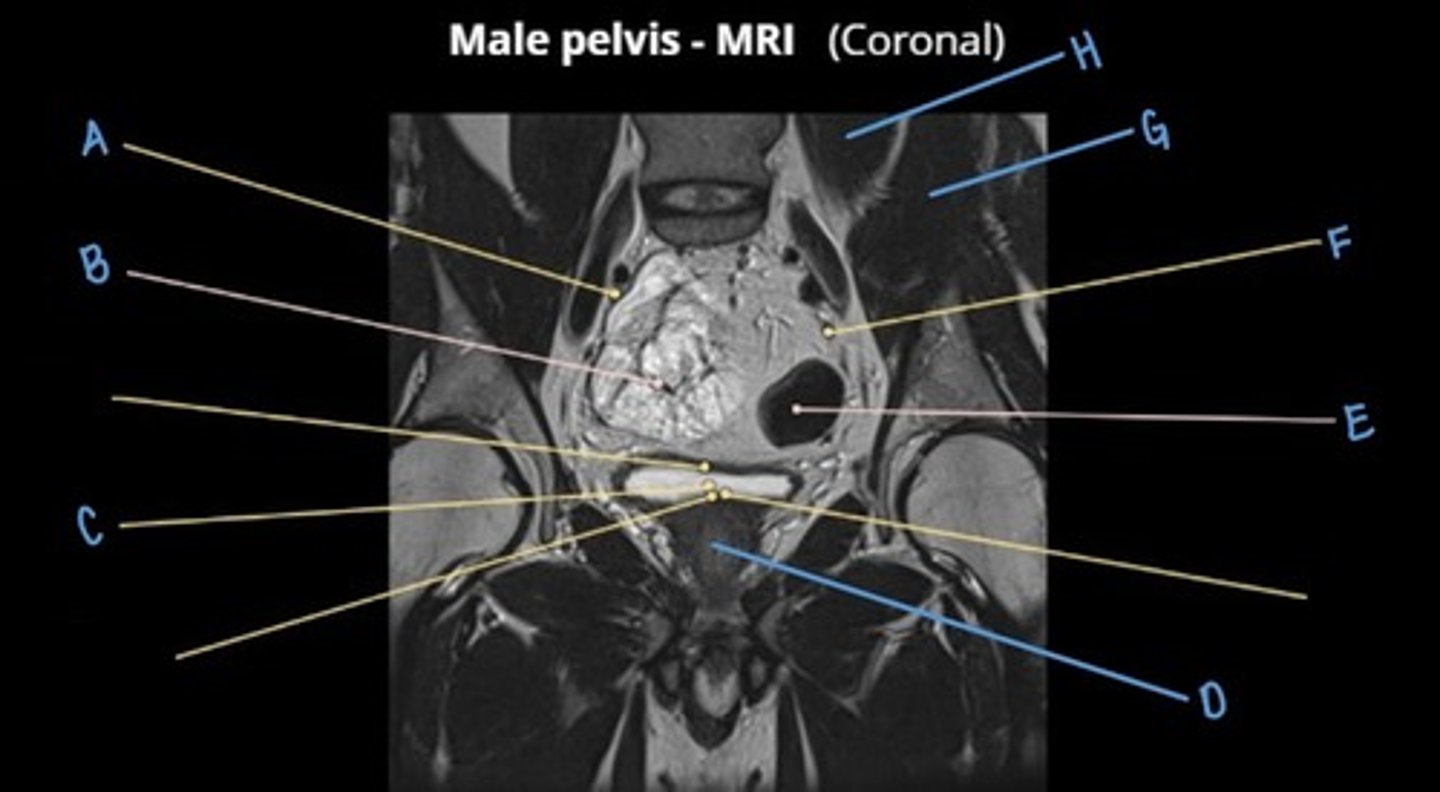

ureter

A & F

small intestine

B

bladder

C

prostate

D

sigmoid colon

E

iliacus muscle

G

psoas major muscle

H